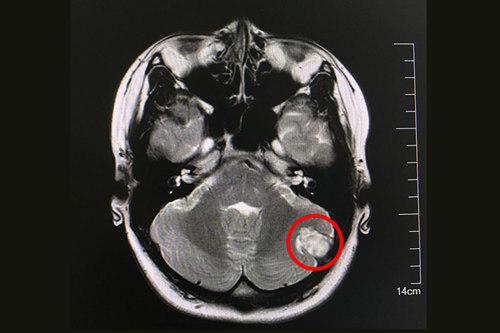

术前核磁显示:左侧后颅窝实性脑外占位病变,与左枕骨宽基相连

在蓝十字脑科医院做了核磁共振等一系列检查之后,侯增欣主任及影像科孙海辉主任等对静静的病情做了讨论,大家提出种种猜测:脑膜瘤?颅骨肿瘤?黄色素瘤?脑脓肿物? 但最后都否定了。唯一不可否认的是,这个病变现在已经从头皮侵入患者小脑,如果不加干预,以后会越长越大,到时将严重影响患者的小脑功能,甚至威胁生命。最后,各位专家一致认为:尽快做手术才是良策。